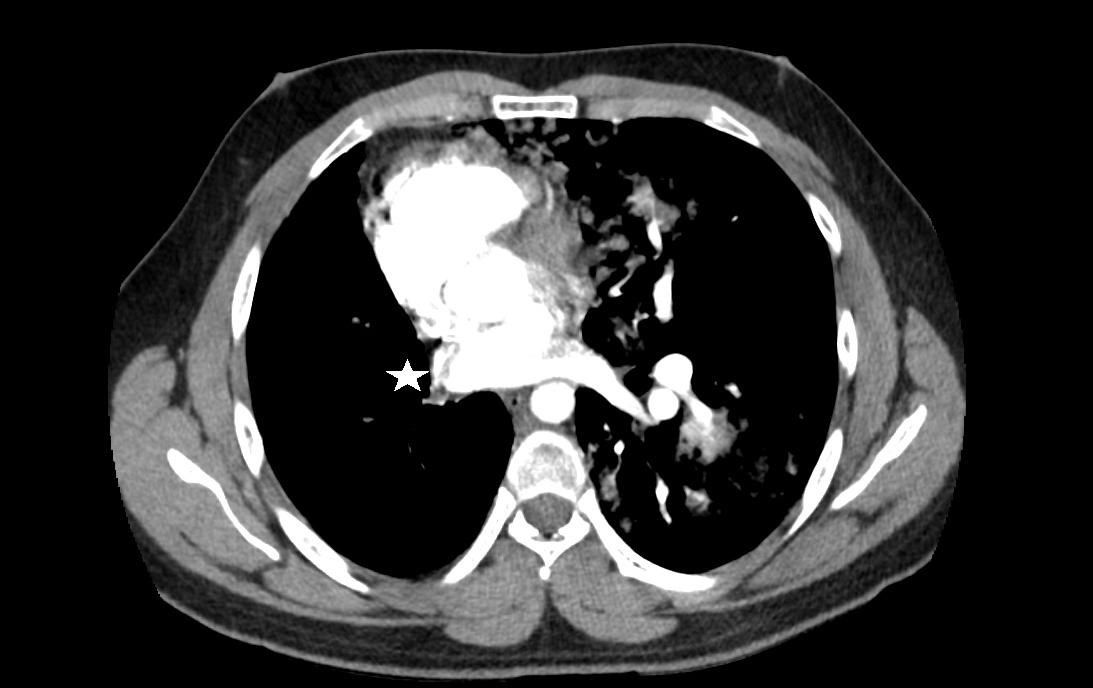

Upon closer inspection, parasternal long-axis view revealed a ventricular septal defect with an overriding aorta and RVH concerning for TOF (Image 2). Parasternal shortaxis cardiac view redemonstrated RVH with interventricular septal flattening indicative of right ventricular pressure

overload from RVOT obstruction (Image 3). Pulmonary ultrasound revealed a normal A-line pattern, and POCUS

Image 2. Parasternal long-axis view of the heart highlighting the findings of a ventricular septal defect (*) with an overriding aorta (Ao) and right ventricular hypertrophy (arrow). LA indicates left atrium; LV, left ventricle; RV, right ventricle.

Image 3. Parasternal short-axis view of the heart notable for interventricular septal flattening (*) due to right ventricular pressure overload in the setting of right ventricular hypertrophy (arrow). LV, left ventricle; RV, right ventricle.